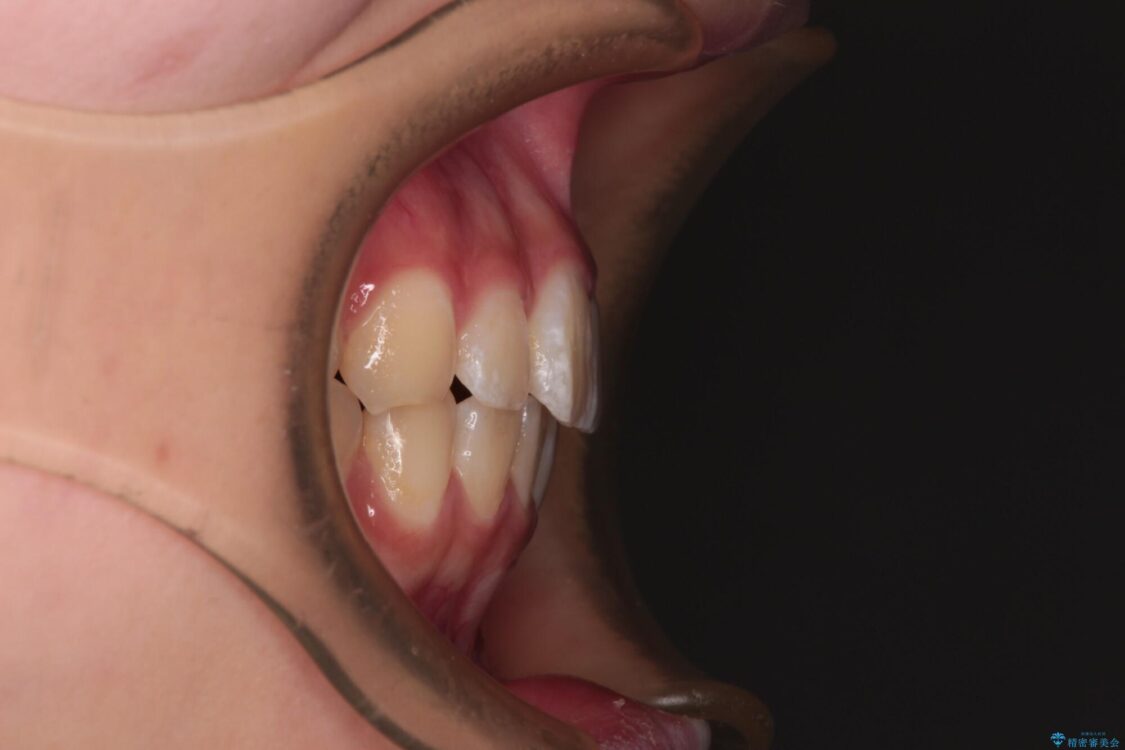

上下前歯のねじれを気にして来院された患者様です。

ワイヤー矯正でもマウスピース矯正でも対応可能でしたが、マウスピース矯正の自己管理が面倒であること、上顎前歯の捻転が著しいことから、ワイヤー矯正での治療を希望されました。

治療前

• インビザラインは使える自信がない ワイヤー装置にて矯正治療 治療前画像